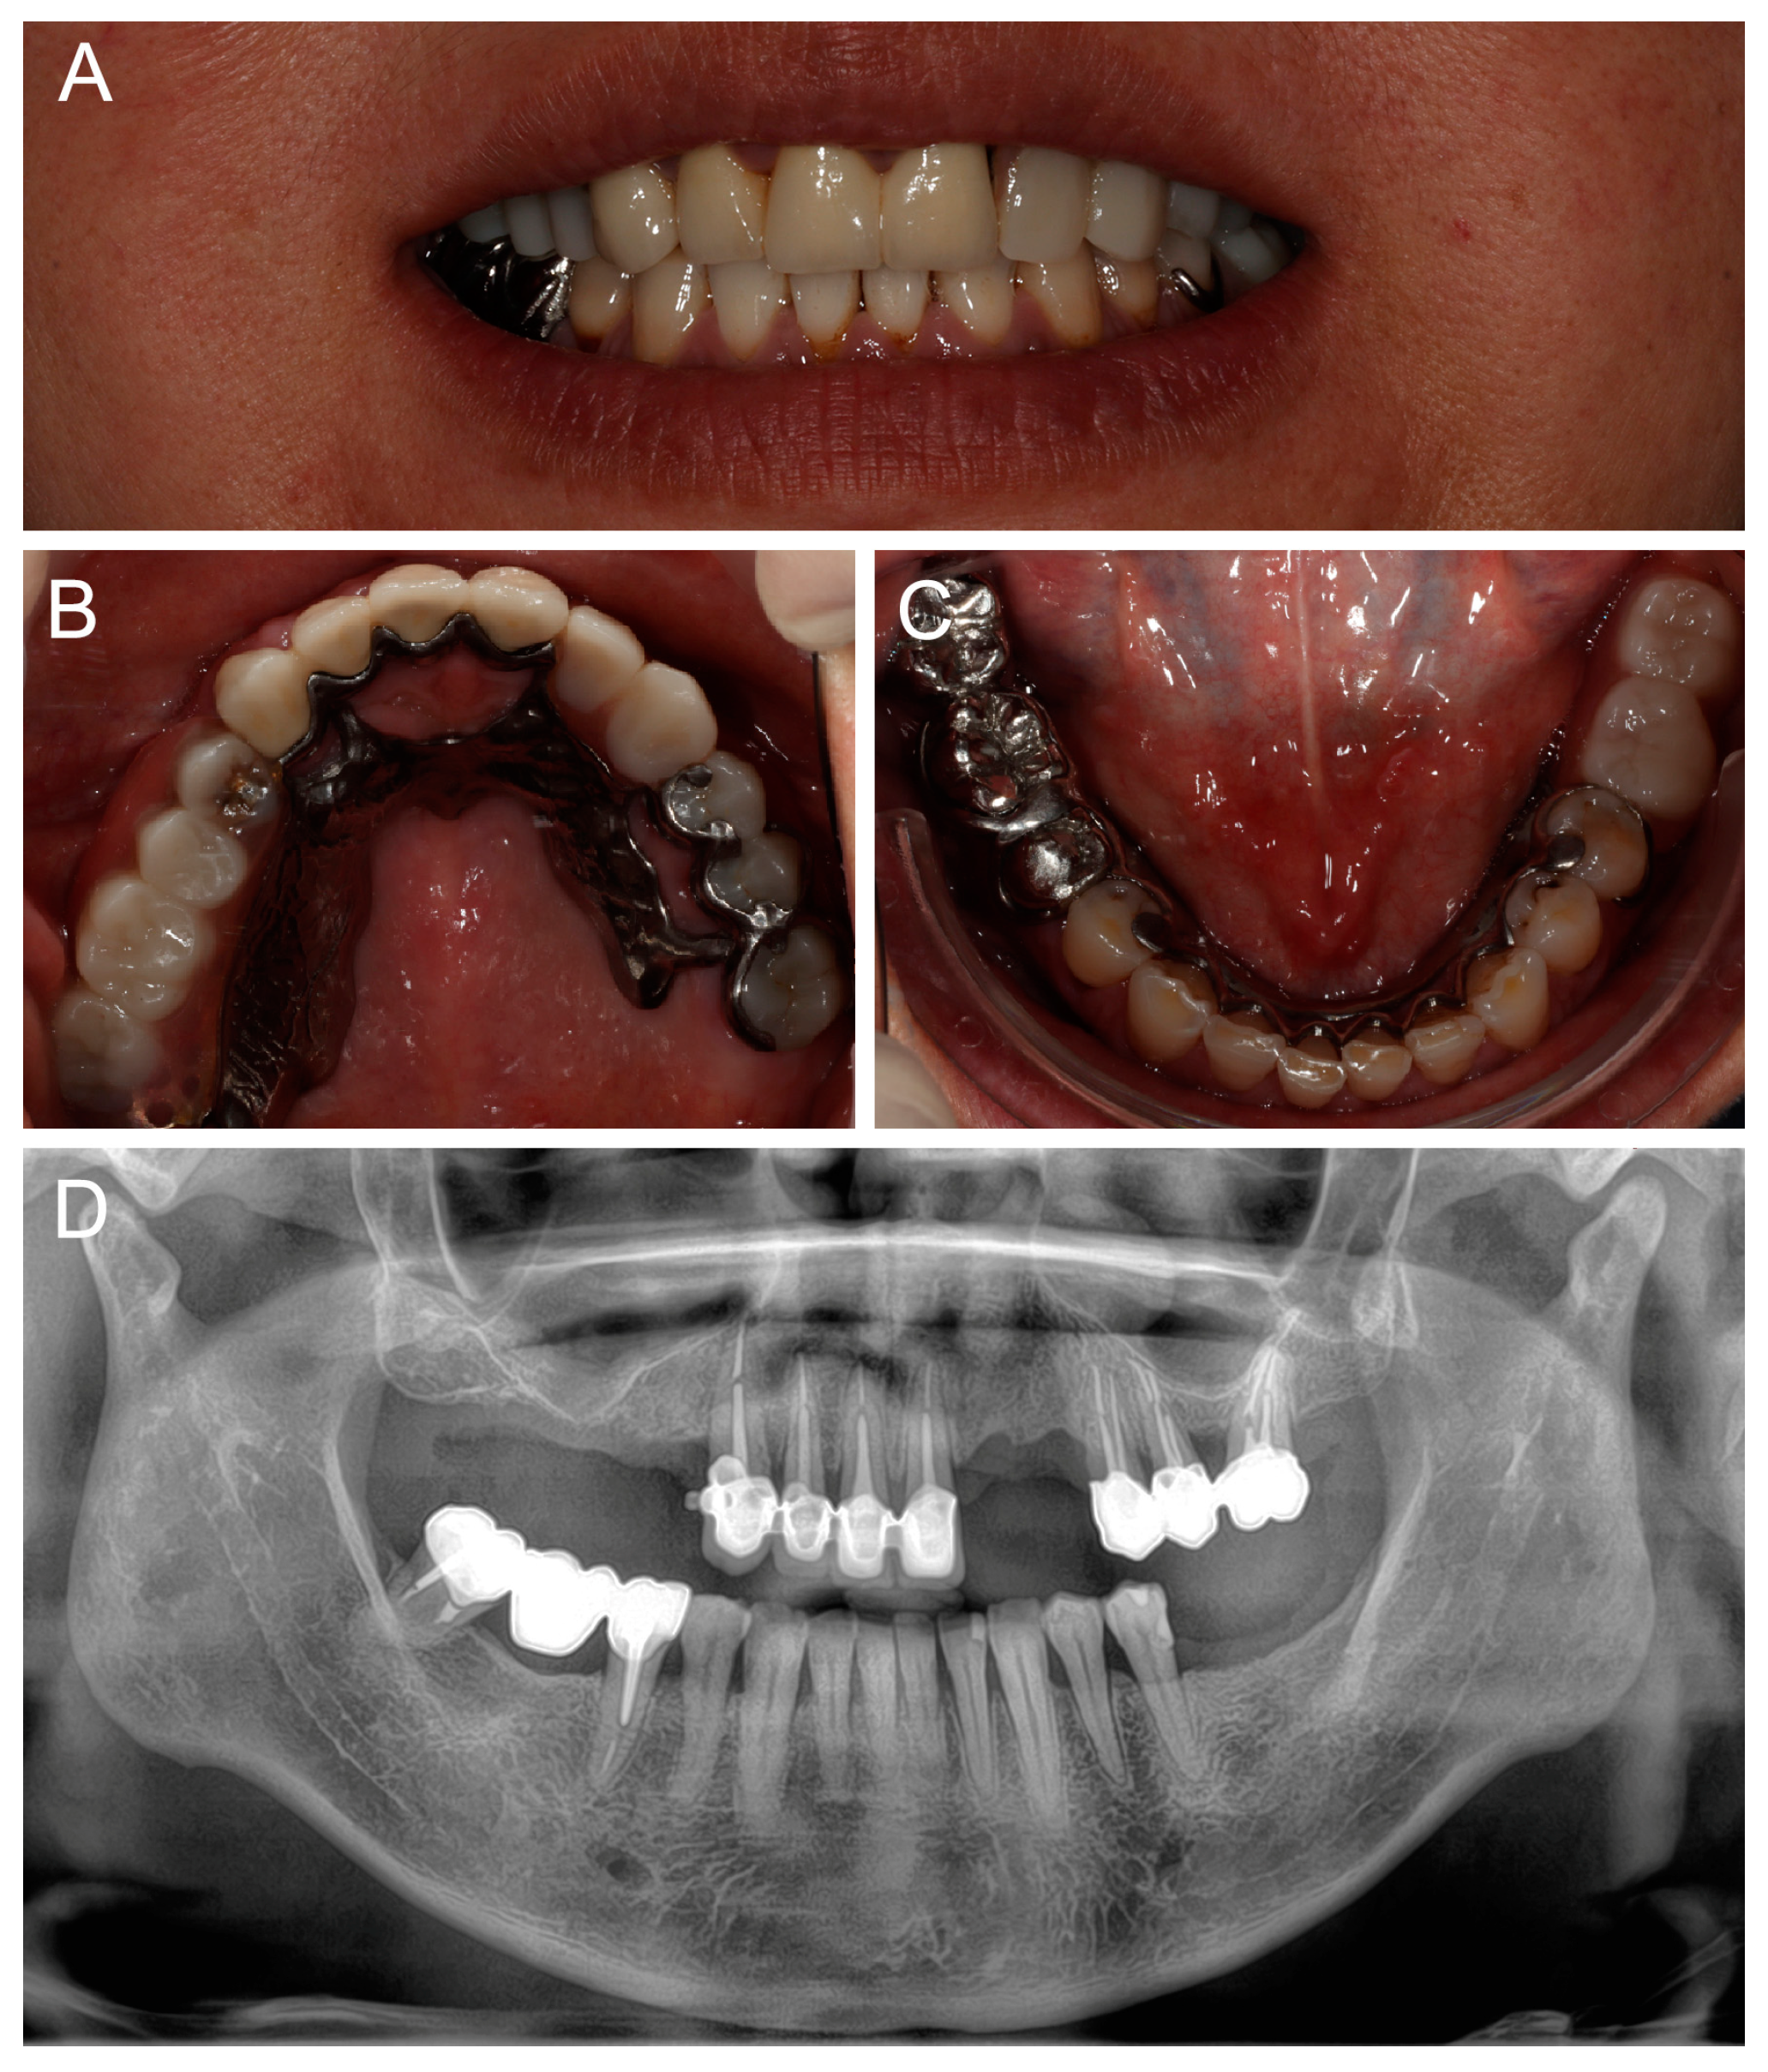

At a 2-year follow-up, the patient was completely satisfied with the rehabilitation and expressed no complaints (Figure 8). The maxillary RPD clasps were slightly retightened on teeth #25 and #26, and standard periodontal maintenance was carried out.

Figure 8.

Follow-up at 2 years: (A) smile view; (B,C) occlusal views of maxillary and mandibular definitive prostheses; and (D) panoramic radiography.